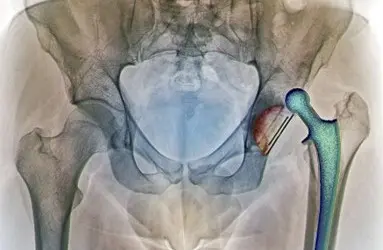

- Total Eklem Protezi (Kalça, diz, diğer)